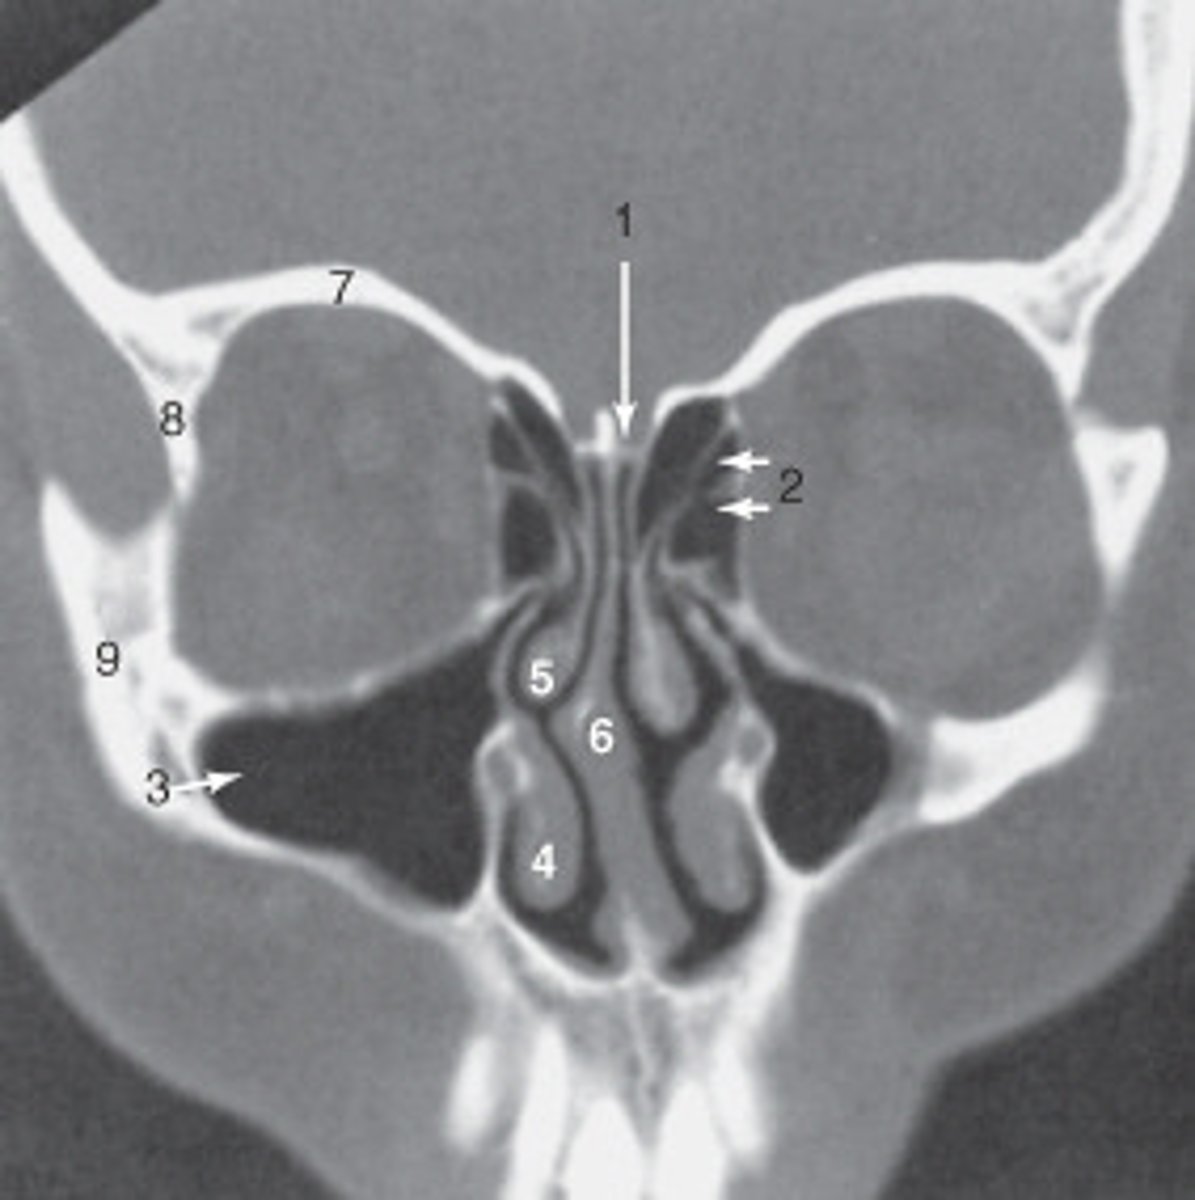

the nasal septum is labeled:

<p>the nasal septum is labeled:</p>

the ethmoid sinuses are labeled:

<p>the ethmoid sinuses are labeled:</p>

the zygoma is labeled:

<p>the zygoma is labeled:</p>

the lateral orbital wall is labeled:

<p>the lateral orbital wall is labeled:</p>

the structure labeled 3 is the:

<p>the structure labeled 3 is the:</p>

roof of the orbit

the structure labeled 7 is the: